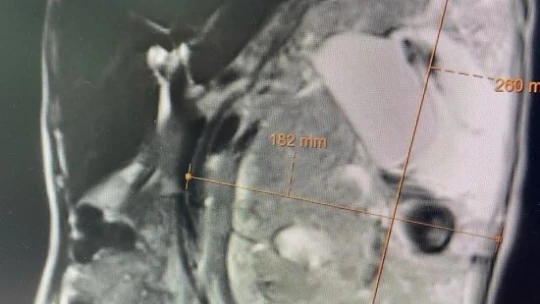

Malatya’da yaşayan işitme ve konuşma engelli olan 63 yaşındaki Beyaz Dinler, bir süre önce korona virüse yakalandı. Bu sürede virüsü aldığı tedavilerle atlatan yaşlı kadının sonrasında çekilen tomografisinde ise böbreğinde 30 santimetre büyüklüğünde tümör fark edildi. İnönü Üniversitesi Turgut Özal Tıp Merkezi’nde Üroloji Servisinde Yrd. Doç. Dr. Hüseyin Çelik ve ekibi tarafından gerçekleştirilen başarılı bir operasyon ile böbrekteki tümöründen kurtulan yaşlı kadının sağlığına kavuştu.

İlk kez böylesine bir büyük tümör ile karşılaştıklarını ifade eden Yrd. Doç. Dr. Hüseyin Çelik, hastanın en büyük şanssızlığının işitme ve konuşma engeli olması nedeniyle yıllardır derdini anlatamadığını ifade etti. Korona virüs sonrası yaşlı hastanın böbreğindeki tümörün tesadüfen fark edildiğini belirten Çelik, tümörün büyüklüğünün kendilerini bile şaşırttığını söyledi.

Normalde böbrek kitlelerinin bu kadar büyük gözükmediğini ifade eden Çelik, “Hastamızın en büyük şanssızlığı hem işitme hem de konuşma engelinin olması ve derdini anlatamaması. Hastamız bir süre önce Covid-19’a yakalanmış. Covid sonrası çekilen tomografide bu kitleye rastlandı. Yaklaşık 30 cm’lik kitleyi ameliyat ile aldık. Ameliyat başarılı geçti. 2 gün yoğun bakımda kaldı. Serviste tedavisine devam ediliyor. Herhangi bir aksilik olmaması durumunda 1-2 güne kadar taburcu etmiş oluruz” diye konuştu.